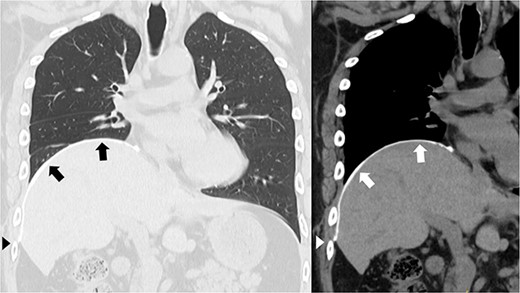

A 41-year-old man was referred to our hospital because of chest pain. Chest computed tomography (CT) revealed an anterior mediastinal tumor, and it was resected by median sternotomy. Pathological diagnosis was thymic cyst. Postoperatively, the patient developed right phrenic nerve palsy due to intraoperative stretch of the nerve and dyspnea on effort. After a year, the phrenic nerve palsy didn’t improve. He then underwent diaphragmatic plication by a right mini-thoracotomy. The elevated diaphragm was resected using an endostapler (Powered Echelon Flex®, black and green cartridges) without any reinforcement. After the second surgery, the surgical stump left by the endostapler ruptured, resulting in diaphragmatic rupture and defect. Chest CT revealed a large diaphragmatic defect (arrowhead) and prolapse of the liver into the thoracic cavity (Fig. 1). However, this condition had been misdiagnosed as the recurrence of diaphragmatic elevation for a year. His dyspnea increased in the supine position, and pulmonary function testing revealed restrictive ventilatory impairment, which led the correct diagnosis of diaphragmatic rupture. The vital capacity (VC) and %VC were 1.86 L and 39.8%, respectively. A year after the second surgery, we then repaired the diaphragmatic defect by right thoracotomy. The surgical view of the thoracic cavity showed that the liver had prolapsed from the large diaphragmatic defect, which measured 15 cm (Fig. 2). Severe adhesion was present between the liver and the edge of the torn diaphragm including the torn staple line and was carefully dissected. The diaphragmatic defect was closed with a 1 mm thick PTFE patch. Moreover, the diaphragm was reconstructed using a second 1 mm thick PTFE patch above the original placement, overlaying the diaphragmatic defect that had been closed by the first PTFE patch (Fig. 3, arrow). The second PTFE patch was fixed to the lower ribs by non-absorbable suture (Fig. 3, arrowhead). The operating time was 325 min, and the blood loss volume was 50 mL. The postoperative course was favorable, and the patient was discharged 7 days after surgery. Three months after the third surgery, his symptoms improved, and pulmonary function testing revealed that the VC and %VC were 2.24 L and 48.1%, respectively. Postoperative chest computed tomography revealed PTFE patch maintained a good position (Fig. 3).

Postoperative chest computed tomography showing the reconstructed diaphragm using a second polytetrafluoroethylene (PTFE) patch above the original placement, overlaying the diaphragmatic defect that had been closed by the first PTFE patch (arrow). The second PTFE patch was fixed to the lower ribs (arrowhead).